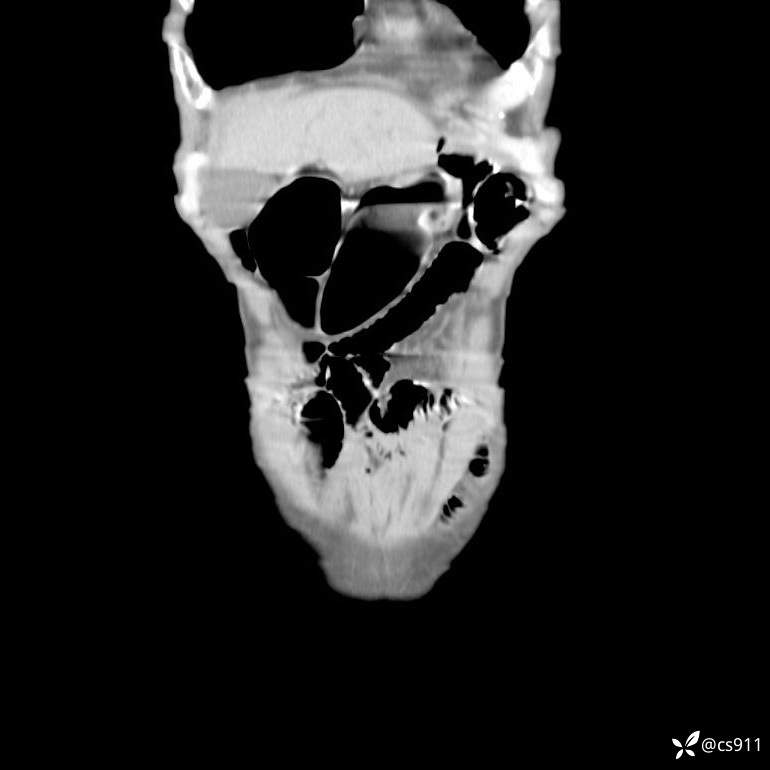

急腹症之急诊CT,原因?答案公布

男,77岁,腹痛、腹胀伴恶心呕吐1天。呕吐胃内容物,非喷射性呕吐,有咖啡色样胃内容物,诉有胃穿孔病史。查体:全腹平,下腹部压痛,全腹无反跳痛,叩诊呈浊音,移动性浊音阴性,肠鸣音减弱,1-2次/分。肛检:直肠未扪及明显肿物,可触及大量粪块。

T 36.6℃ P 80次/分 R 26次/分 BP 100/60mmHg

白细胞(WBC) H 14.55 10e9/L 4-10

中性粒细胞百分率(NEUT%) H 85.7 % 40-75

血淀粉酶(AMY) HH 1859 U/L 35-135

癌胚抗原(CEA) H 27.44 ng/ml 0-5

呕吐物 潜血试验 * 阳性 阴性

患者轮椅入室检查神志清楚, 能配合摆位和呼吸